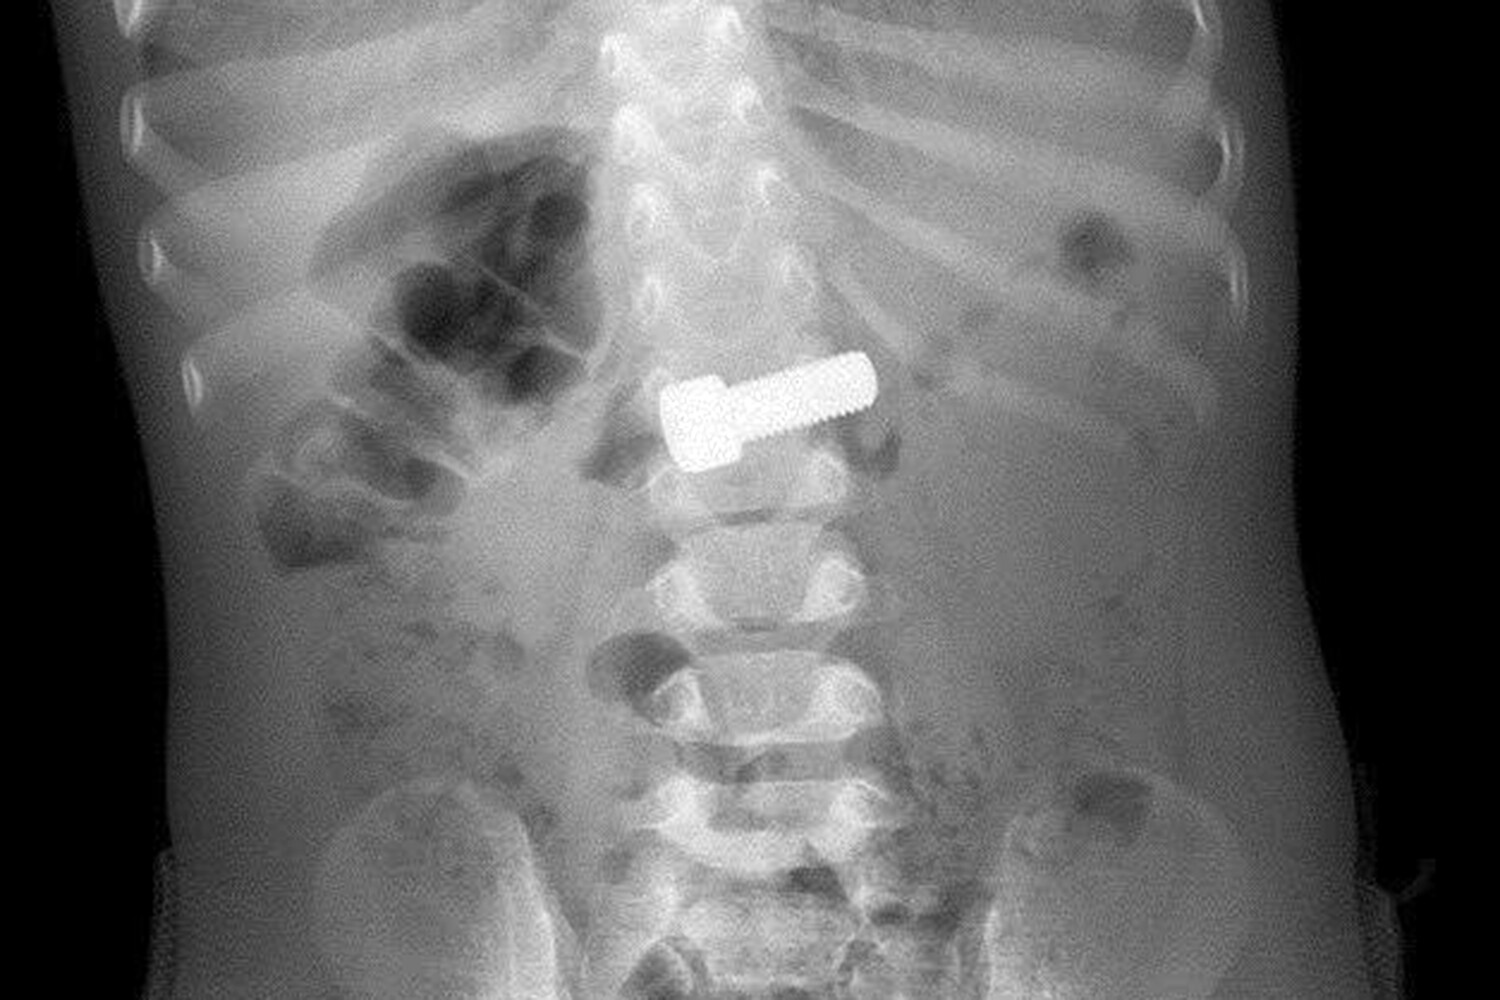

Годовалый ребенок играл и случайно проглотил болт, родители сразу вызвали скорую помощь. В приемном отделении ребенку сделали рентген, который подтвердил нахождение инородного тела в желудке. Врачи-эндоскописты оперативно провели процедуру по извлечению предмета с помощью специальной петли, которая заняла около 15 минут.